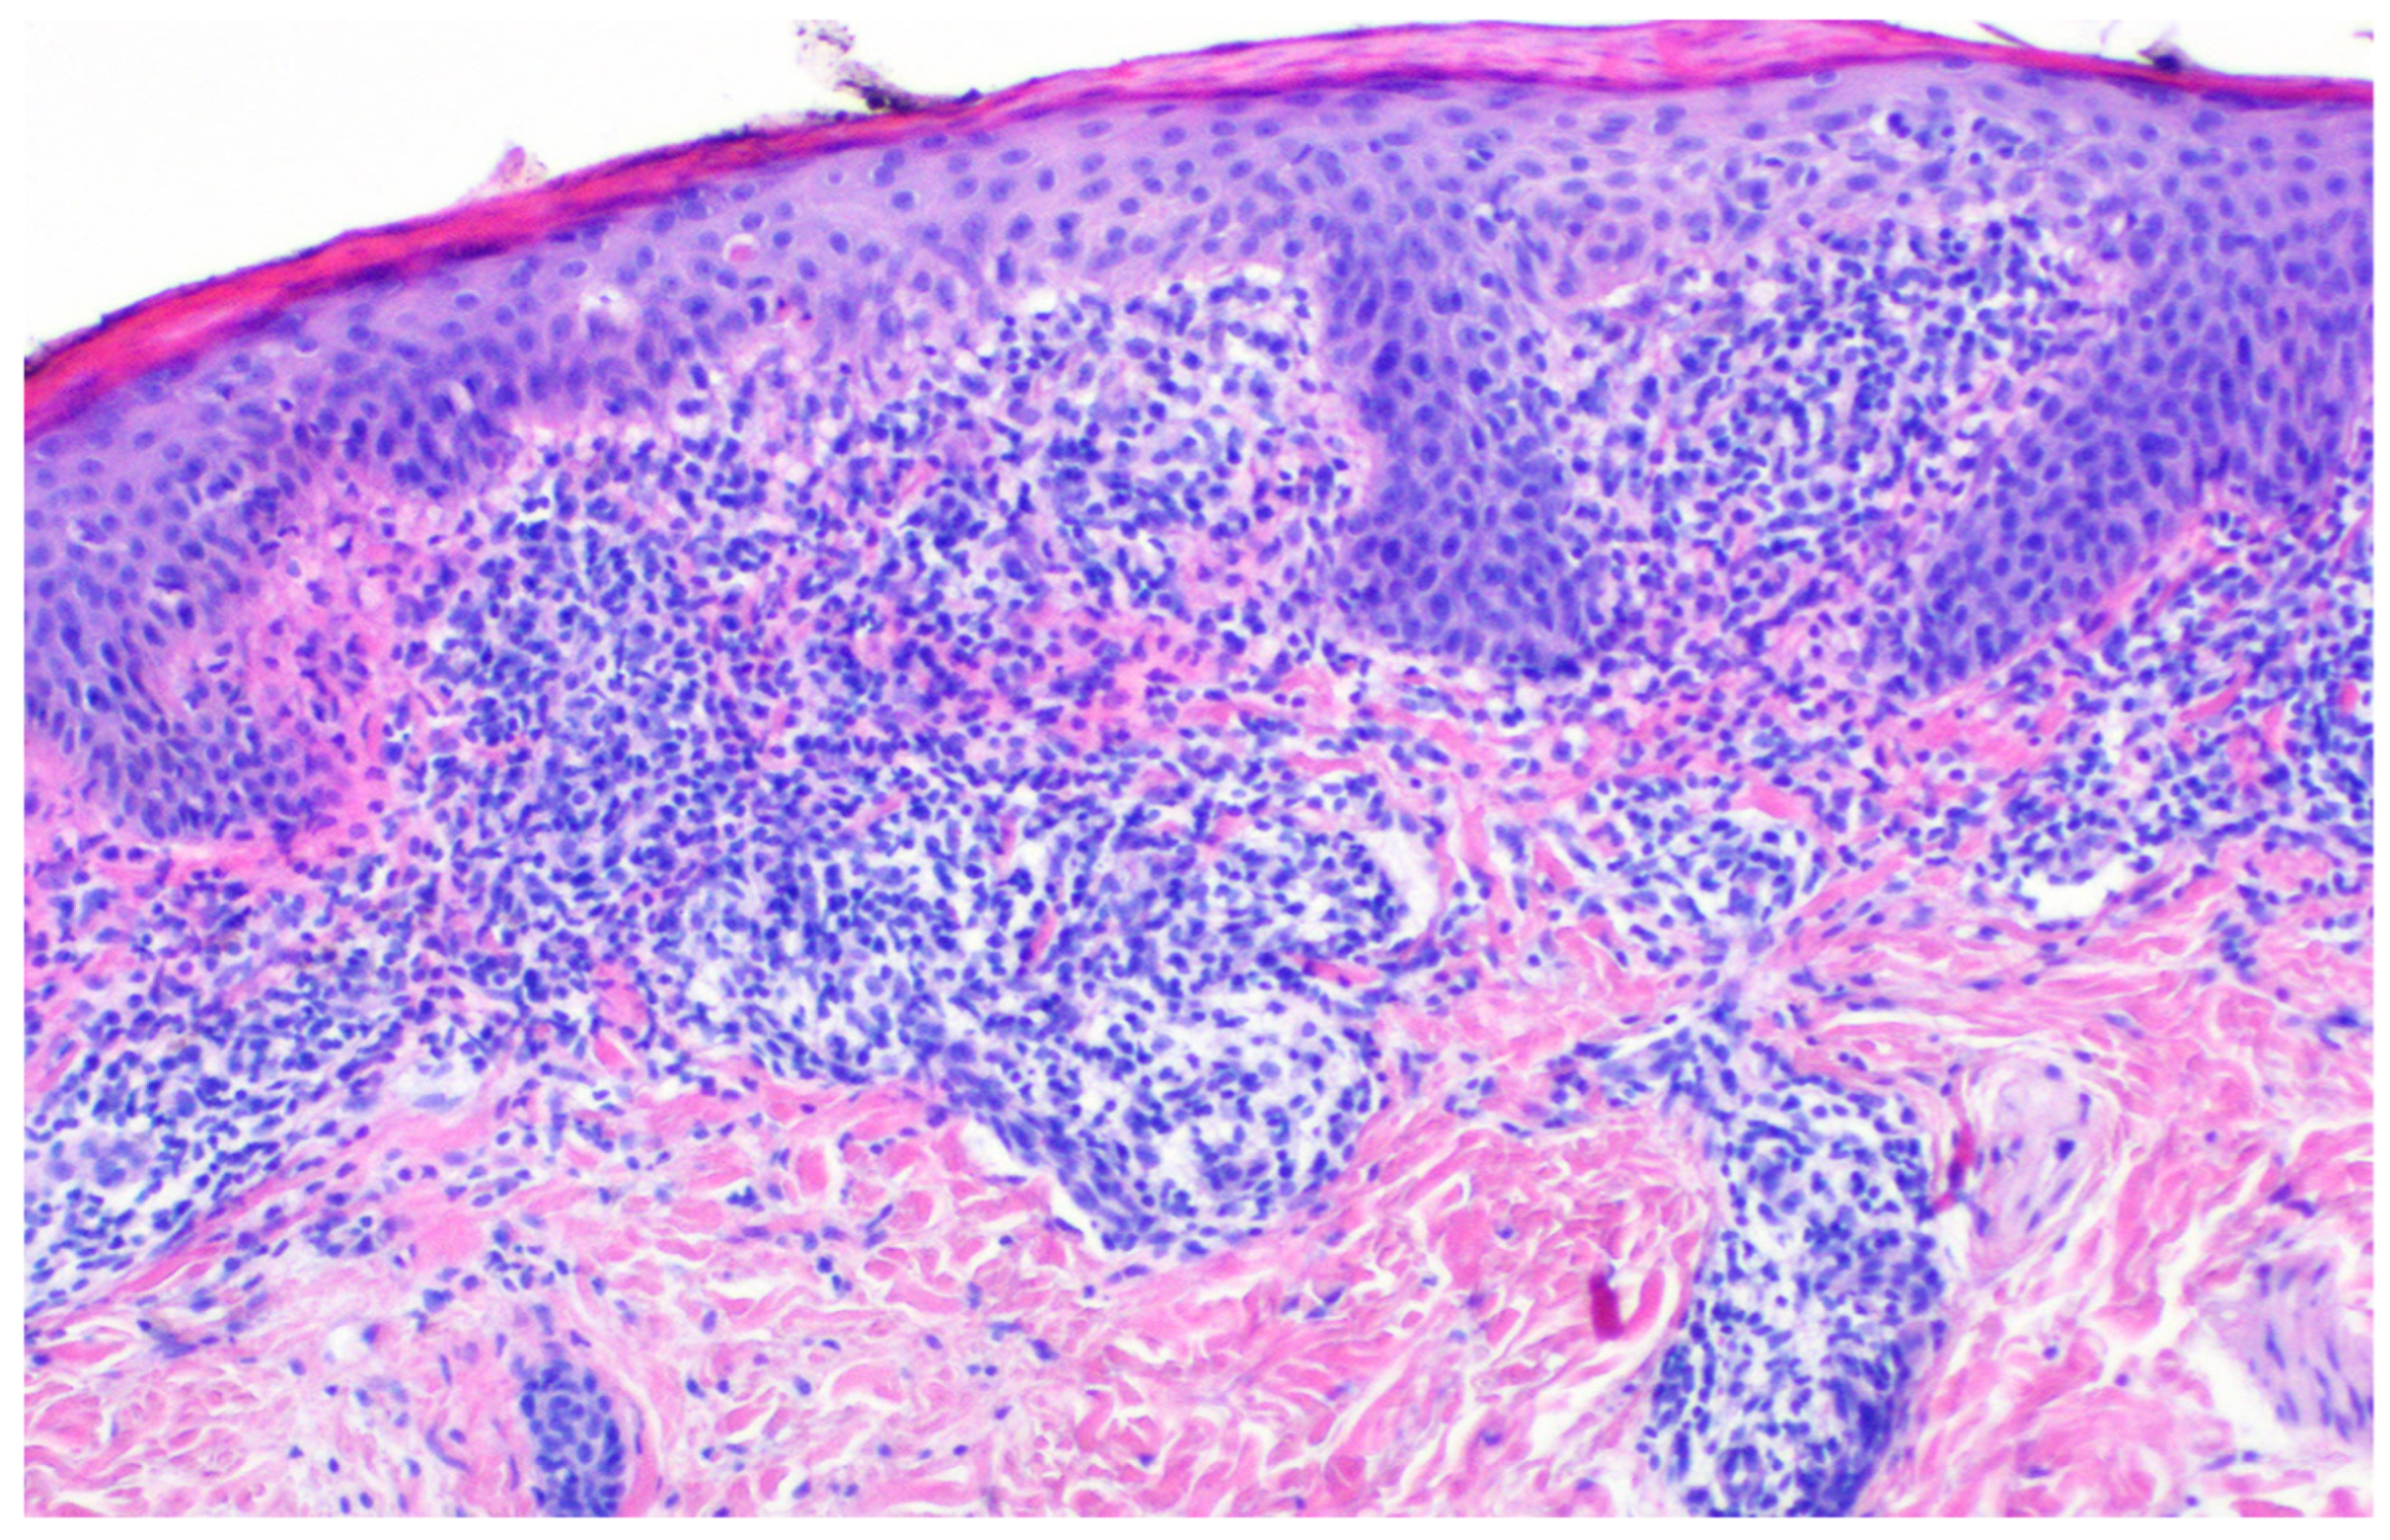

| Dermis | Dense, band-like lichenoid infiltrate at the dermoepidermal junction (DEJ) (similar to LP) associated with perivascular and periappendagealinflammatory infiltrate–involvement of eccrine glands and ducts distinguishes LS from other lichenoid dermatosies [3]. | Less lichenoid pattern; minimal eccrine involvement [8,9]. | Mild superficial perivascular infiltrate; less prominent than in LS [10,11]. | Dense, band-like lichenoid infiltrate along the DEJ; involvement limited to the upper dermis [12,15]. | Thickened, hyalinized collagen bundles; loss of adnexal structures; perivascular lymphocytes [13]. | Absence of extracellular melanin (no signs of pigment leakage). No histological signs of inflammatory infiltration [14]. |